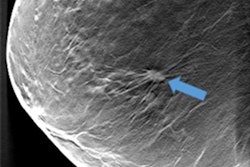

Rodríguez-Ruiz and colleagues compared the performance of a commercial deep-learning computer detection system (Transpara version 1.2.0, ScreenPoint Medical) with that of radiologists in detecting breast cancer on digital mammography images. The study included 24 radiologists who retrospectively reviewed 1,435 two-view digital mammography exams, 336 of which were malignant (23%) and 430 of which were benign (30%). The radiologists ranked the exams on a scale of 0 to 10, with 0 indicating no lesion was present and 10 indicating a lesion that was "definitely malignant."

The group then applied a deep-learning algorithm to the mammogram dataset. The algorithm identifies soft-tissue and calcified lesions and combines the findings of all available views into a single cancer suspiciousness score (based on the same scale the readers used). Finally, Rodríguez-Ruiz and colleagues calculated the area under the receiver operating characteristic curve (AUC) for both the radiologist readers and the algorithm.